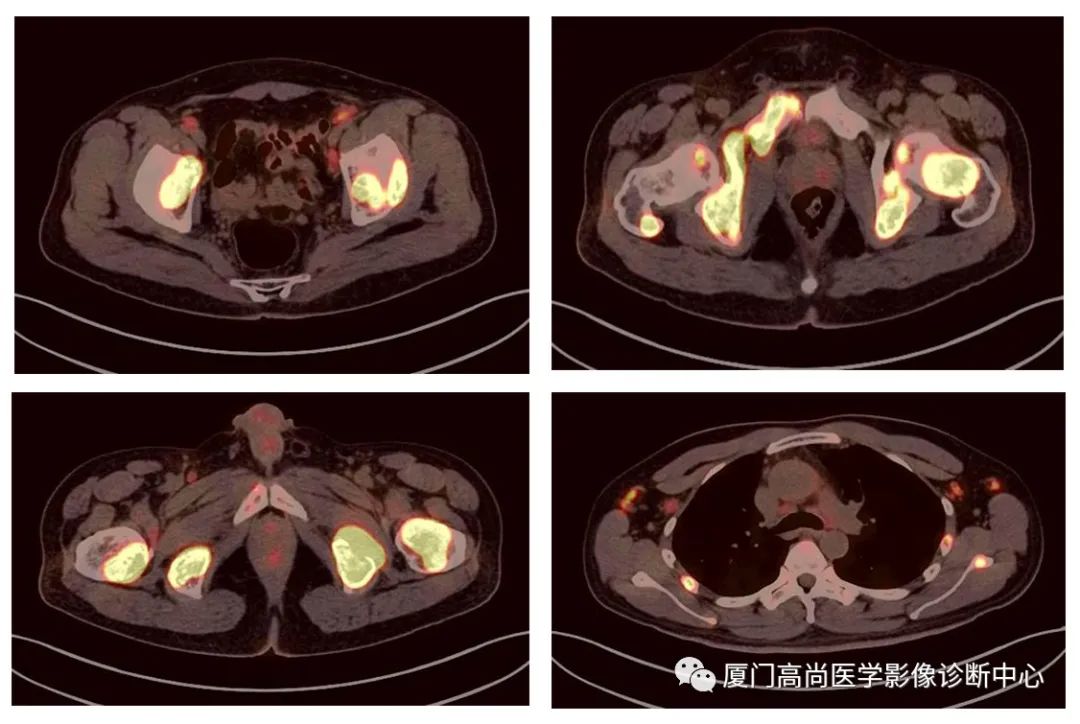

病例2、某女士,62歲,近3個(gè)月來自覺消瘦,無其他自覺癥狀,CT發(fā)現(xiàn)雙側(cè)腎上腺增大,性質(zhì)待定,查血各項(xiàng)腫瘤標(biāo)記物均正常,臨床診斷不清,申請(qǐng)做PET/CT檢查

腹腔淋巴結(jié)腫大

小腸多段淋巴瘤病灶

PET/CT發(fā)現(xiàn) :左心房、右心房見團(tuán)塊狀FDG攝取增高;雙側(cè)腎上腺增大,F(xiàn)DG攝取增高;膽囊和胃壁結(jié)節(jié)樣FDG攝取增高;小腸多節(jié)段腸壁增厚,F(xiàn)DG攝取增高;腹膜后、腹腔及盆腔多發(fā)淋巴結(jié)腫大,F(xiàn)DG攝取增高;上述考慮為淋巴瘤

經(jīng)腎上腺穿刺活檢 :病理證實(shí)為彌漫大B細(xì)胞淋巴瘤